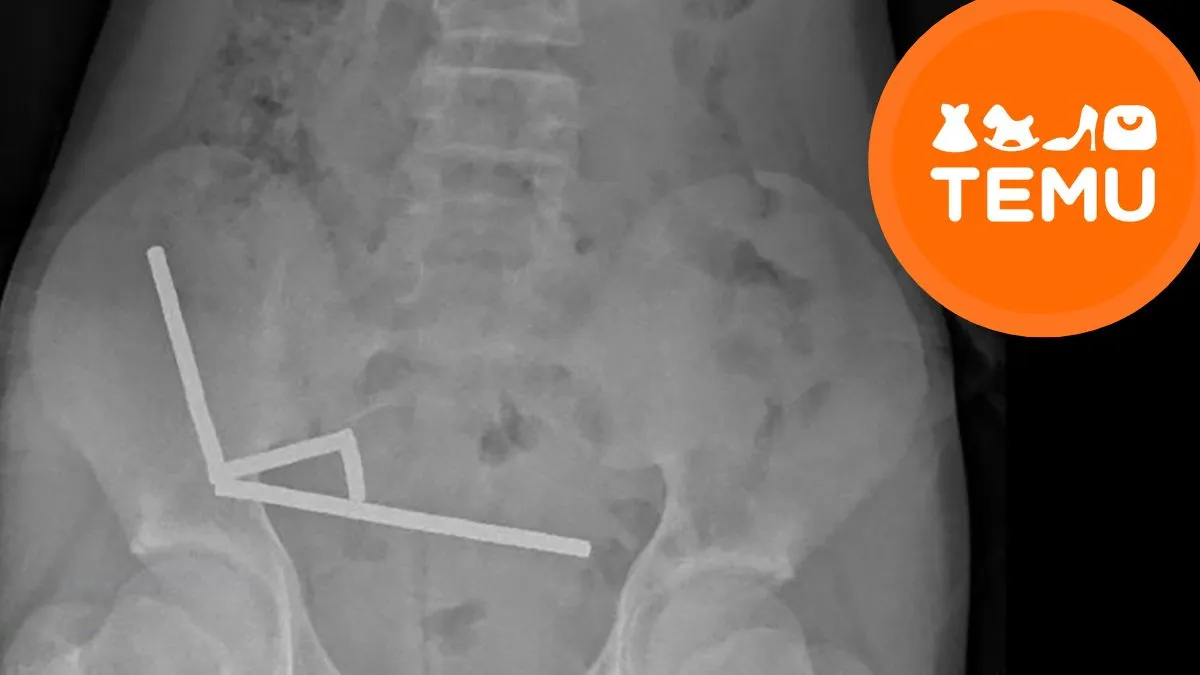

जेव्हा डॉक्टरांनी एक्स-रे काढला तेव्हा त्यांना काहीतरी भयानक दिसले. त्याच्या आतड्यांमध्ये चार लांब रेषांमध्ये चुंबक एकत्र जमले होते. त्यांच्यातील शक्तीने त्याच्या आतड्यांचे काही भाग एकत्र खेचले, रक्त प्रवाह बंद झाला आणि अनेक ठिकाणी ऊती नष्ट झाल्या. यामुळे डॉक्टरांनी “नेक्रोसिस” म्हटले, म्हणजे त्याच्या आतड्याचे काही भाग मरण्यास सुरुवात झाली.